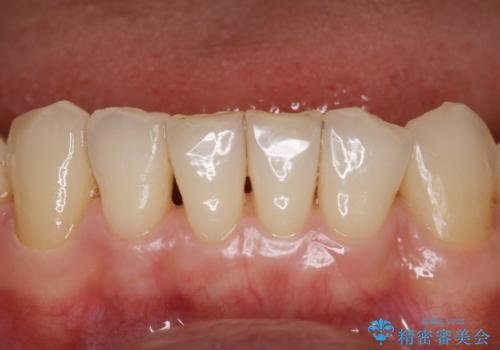

- 治療計画

- インビザラインで矯正中の患者様です。リファインメントのタイミングでホームホワイトニングをご希望でしたが、歯の表面にステインがかなり付着していたため、エアフローでのクリーニングからお勧めしました。

歯の表面にステインやバイオフィルムが付着していると、歯面がざらつき更に汚れが付きやすくなるだけでなく、付着物の影響でホワイトニング薬剤の浸透が悪くなりトーンアップ効果が減少します。歯の表面の汚れを落とすことで歯面もツルツルになり、ホワイトニングを行わなくても歯が白くなった様に感じられる場合もあります。

エアフローだけで歯が白くなったと喜んでいらっしゃいました。新しいマウスピースが届くまでの間はホームホワイトニングを行い歯の内部から白くしていきます。